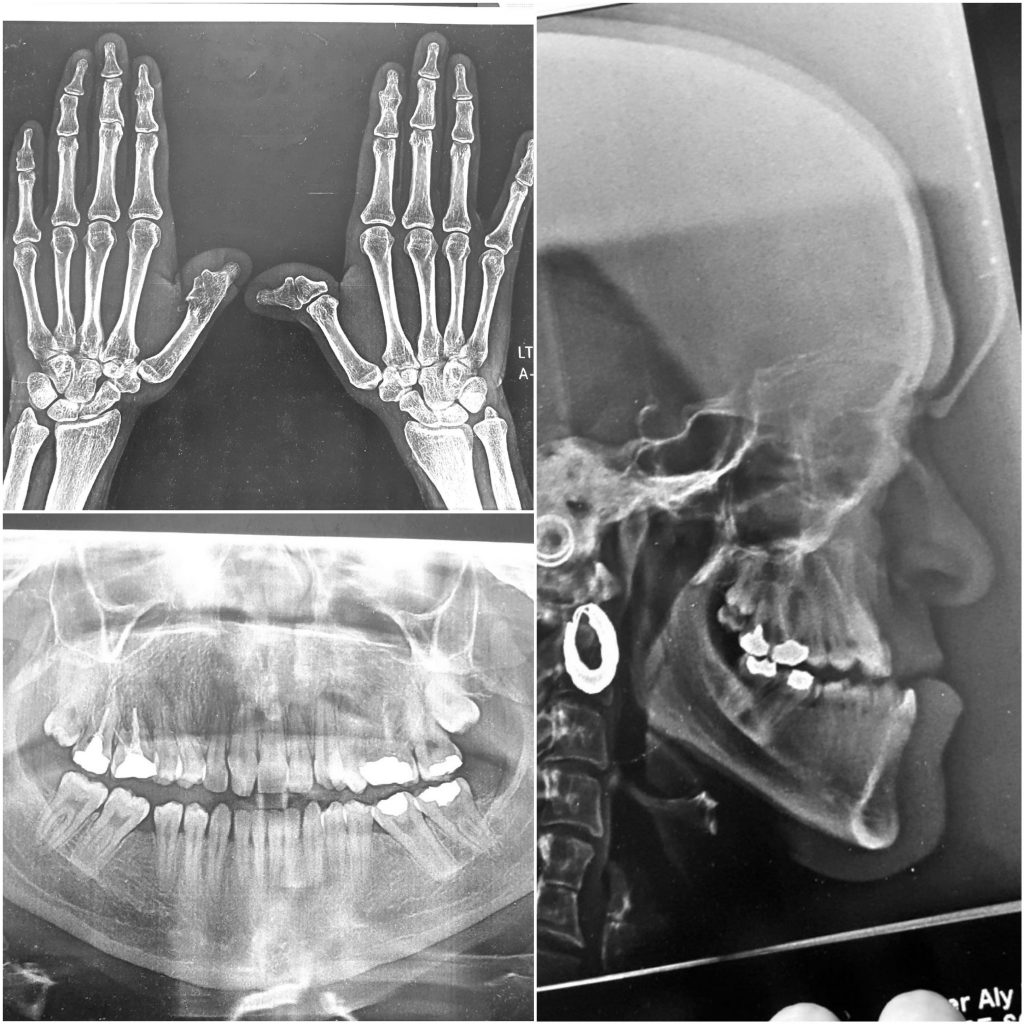

* Extraoral : she has the features of “pfeiffer dyndrome”( one of craniocynestosis syndromes ), concave , class III facial pattern , sever midface deficiency , hypertelorism , broad and malformed thumbs .

*Intraoral : incisors cl III complicated with sever crowding in upper arch , extracted UR3 , LR and LL 6s , anterior and posterior crossbite , upper midlineshift to the right , multiple restorations and fair OH

B. Surgery : bimax surgery , modified Lefort 1 osteotomy with maxillary advancement , Bsso with mandibular setback .